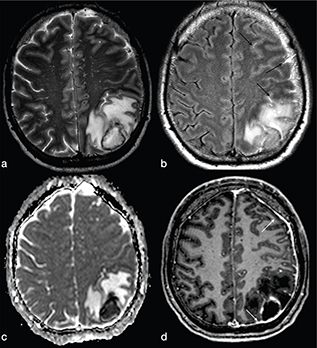

On FLAIR/T2-wi, the abscess is usually surrounded by vasogenic oedema. Moreover, FLAIR images can be useful to help improve the diagnosis of a subarachnoid rupture of the BA with subsequent meningitis (Figure 3). Satellite abscesses that give a polylobate appearance to the BA can occur (Figure 4).

FIG 3. A 45-Year-Old Man with Pyogenic Abscess Surfacing the Left Parietal Lobe Cortex. A roundish mass with a core of necrotic-cystic degeneration (a–b) showing restricted diffusion on ADC maps (c) and diffuse surrounding vasogenic oedema (a–c) with irregular rim-enhancement (d) is shown. FLAIR-T2w (b) high signal within the subarachnoid spaces reveals rupture of abscess into the subarachnoid space (black arrows in b). Meningeal involvement is also appreciable after i.v. administration of Gd (white arrows in d).

FIG 4. A 54-Year-Old Woman with Multiple Pyogenic Abscesses Involving the Right Thalamus and Right Temporal Region. The abscesses show a thin capsule on T2w (a) binding a core of restricted diffusion (asterisk in b) with correspnding low signal in ADC maps (c). Smooth ring enhancement on gadolinium-enhanced T1w (d) is present. Satellite abscesses (black and white arrows in a and d respectively) give a polylobulated appearance.